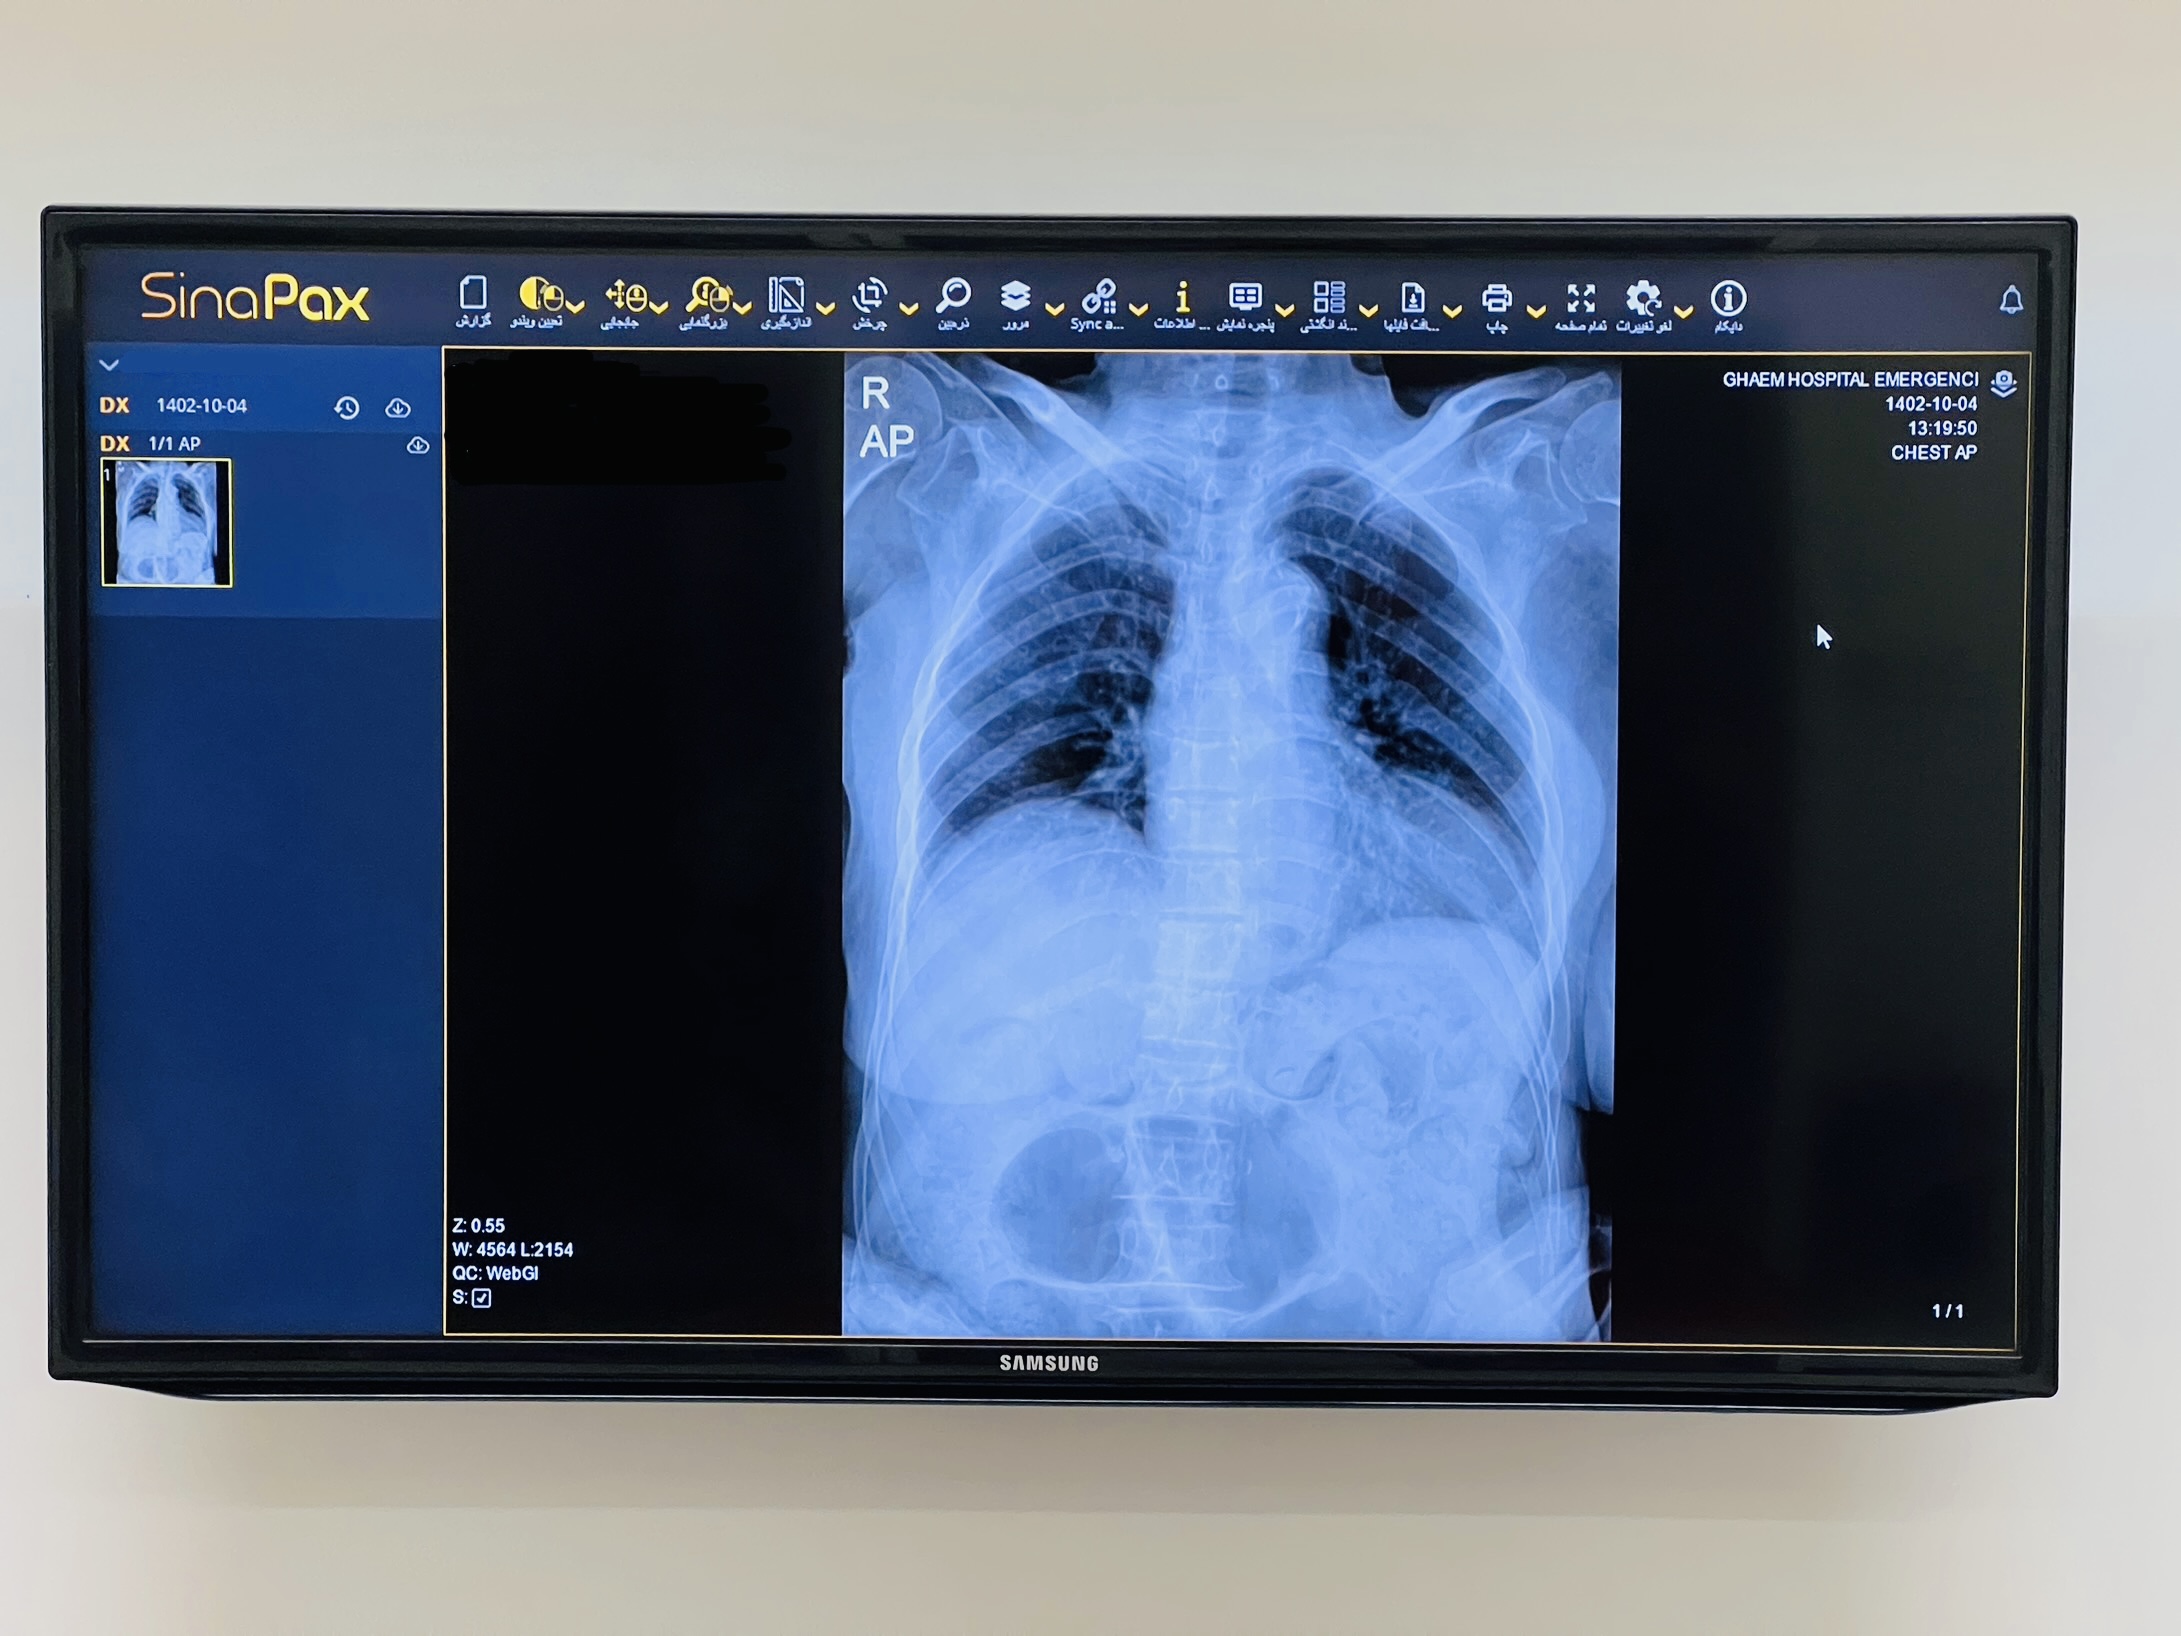

نحوه استفاده از سیستم PACS |

معرفی سیستم PACS (picture archiving and communication system) |

سیستم پکس به معنای سیستم بایگانی و ارتباطات تصاویر پزشکی است. در واقع یک فناوری تصویربرداری پزشکی می باشد که بازیابی، ذخیره، توزیع و ارائه تصاویر پزشکی را انجام می دهد. از سیستم PACS برای انتقال دیجیتالی تصاویر و گزارش های الکترونیکی استفاده می شود. یک فرمت جهانی برای ذخیره و انتقال تصاویر PACS وجود دارد که DICOM نام دارد. DICOM فرمتی است که برای تصاویر دیجیتال و ارتباطات دستگاه های پزشکی مورد استفاده قرار می گیرد. این فرمت برای سیستم های پکس، RIS و سایر سیستم های تصویربرداری پزشکی برای انتقال داده ها و سایر امکانات مورد استفاده قرار می گیرد. اکثر سیستم های PACS معمولاً دستورالعملهای تصویربرداری پزشکی زیادی مانند اولتراسوند(یکی از ابزارهای پر کاربرد مورد استفاده در فیزیوتراپی)، رزونانس مغناطیسی، توموگرافی گسیل پوزیترون، توموگرافی کامپیوتری، تصویربرداری پزشکی هستهای، ماموگرافی، آندوسکوپی، رادیوگرافی دیجیتال، هیستوپاتولوژی، رادیوگرافی کامپیوتری، چشمپزشکی و چندین مورد دیگر را انجام میدهند. در این سیستم، انواع بیشتری از قالب های تصویربرداری، هر زمان که لازم باشد اضافه میشوند. همچنین مراکز بالینی که فراتر از رادیولوژی هستند، مانند ارتوپدی، انکولوژی، قلب عروق که تصاویر پزشکی ارائه می دهند به راحتی می توانند در سیستم PACS گنجانده شوند. در حال حاضر دانشکده پزشکی با دو بیمارستان امام رضا (ع) و قایم (عج) به منظور آموزش و تدریس تصاویر رادیولوژی با استفاده تصاویر و آرشیو های سیستم پکس این دو بیمارستان همکاری دارد. |